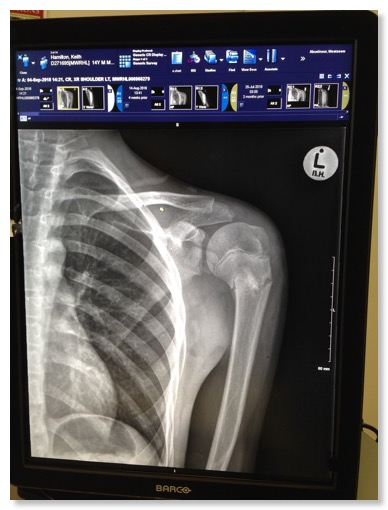

At the beginning of the month, our oldest boy had a doctor’s appointment for the arm he broke in July during the Teen Rally. He was told his arm was finally healing, but that he cannot do any strenuous work for six months. At the end of the month, our youngest had his seventh birthday. We were able to take him to an indoor play area, and Kelly made him his favourite meal—pancakes.